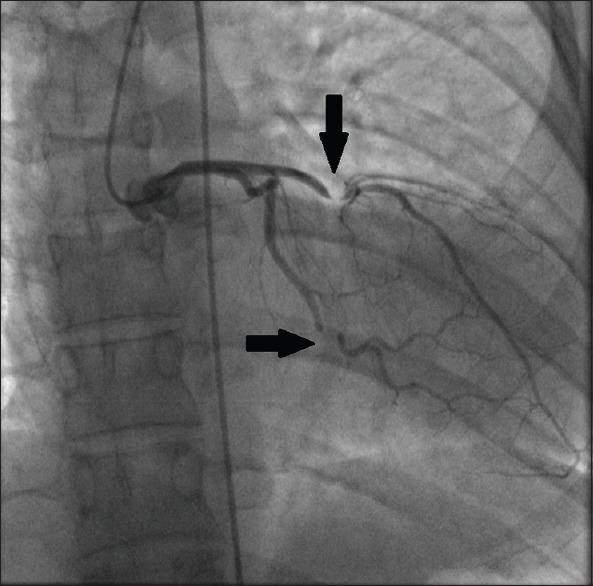

医源性心包缺损

Iatrogenic pericardial defect.

Pericardial defects are uncommon, usually congenital, and frequently involve a complete absence of the pericardium. Partial pericardial defects are more likely to result in complications. Iatrogenic pericardial defects are usually partial defects and may present with cardiac strangulation. We present the case of an iatrogenic pericardial defect in an asymptomatic 20-year-old female.

心包缺损并不常见,通常为先天性,且常表现为心包完全缺失。部分心包缺损更易引发并发症。医源性心包缺损通常为部分缺损,可能会出现心脏绞窄。我们报告了一例20岁无症状女性医源性心包缺损的病例。